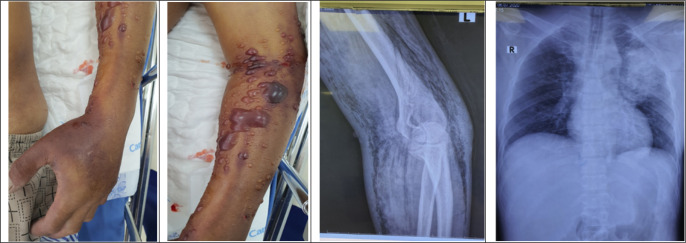

Aeromonas hydrophila has been identified as a causative agent of necrotizing fasciitis and myonecrosis, with most reported cases having a connection to aquatic-related trauma. Cases without such trauma history are rare in existing literature. Here, we present the case of a 56-year-old cirrhotic patient who lacked any prior aquatic-related trauma and arrived at the emergency department in a state of septic shock. The suspected route of entry was through necrotizing fasciitis and myonecrosis in his left forearm. Unfortunately, the patient succumbed to multi-organ failure and passed away within 12 hours of admission to the emergency department.

Abstract Image